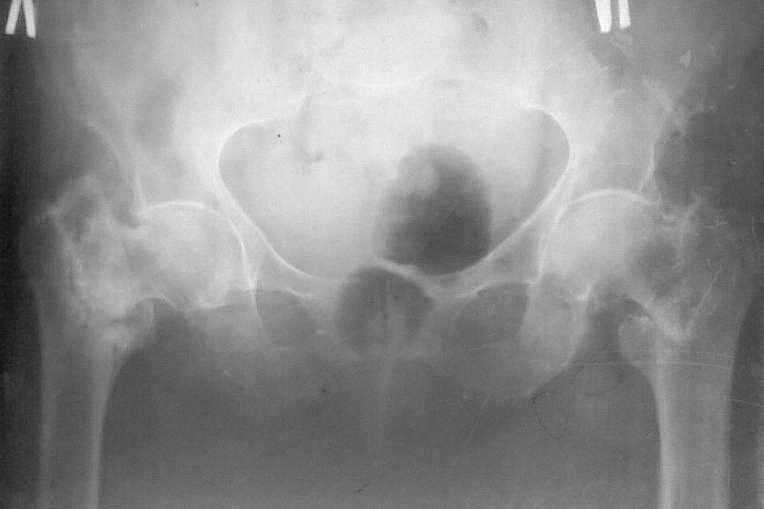

Поступила больная 80 лет, справа перелом свежий, слева - 4 летней давности.

Здравствуйте,уважаемые коллеги! Поступила больная 80 лет, справа перелом свежий, слева -

нелеченный перелом 4х-летней давности. Больная проживает в частном доме, до последней

травмы передвигалась с костылями, себя обслуживала.Соматически сохранна. Помогите

выбрать оптимальную тактику лечения (Гамма недоступна) Наши варианты : 1. Справа DHS, слева

- МВО, промежуток между операциями - 10 -12 суток 2. Справа DHS , слева - не трогать 3. Справа DHS

. слева протез Мура после скелетного вытяжения (?) Я больше склоняюсь к третьему

варианту,поскольку установка протеза позволит максимально быстро поднять больную.